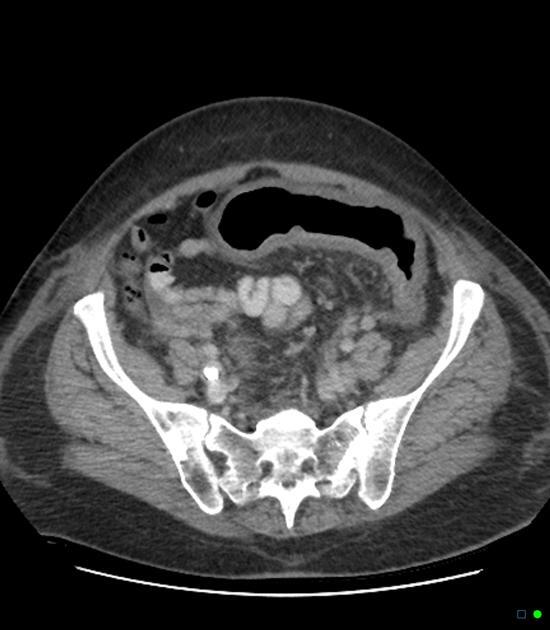

Paciente pós QT. HD?

A

Tiflite (enterocolite neutropênica).

Espessamento da parede do ceco, estrias na gordura pericecal , pneumatose intestinal (gás na parede intestinal) em paciente imunossuprimido.